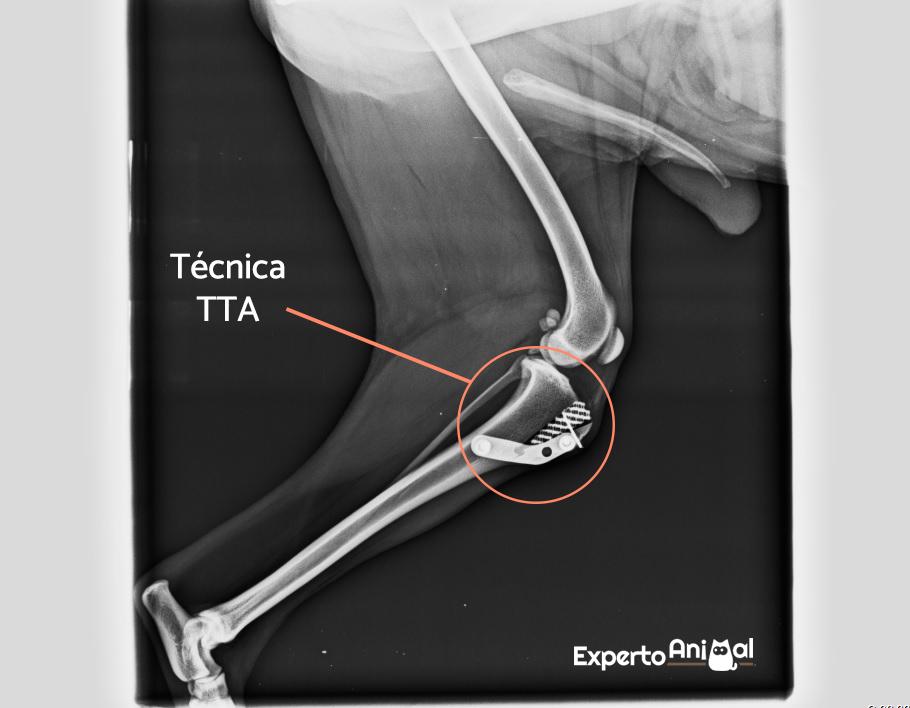

- Técnicas de osteotomía, más modernas, consistentes en modificar las fuerzas que permiten mover y mantener estable la rodilla. En concreto, cambian el grado de inclinación de la meseta tibial con respecto al ligamento rotuliano, lo que permite que la rodilla articule sin utilizar el ligamento dañado. Son técnicas como la TTA (adelantamiento de la tuberosidad tibial), la TPLO (osteotomía de nivelación de la meseta tibial), la TWO (osteotomía en cuña) o la TTO (triple osteotomía de la rodilla).

Hola , soy Niña y mi perro fue operado con la técnica TTA del LCA el día 1/03/2021 . La operación salía muy bien y a los 4 hora apollaba la punta de los dedos en el suelo .